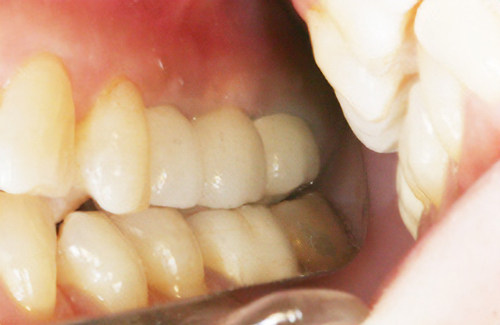

• 審美面も機能面でも回復

インプラントとは、失ってしまった歯の代用として、人工歯根=インプラントを埋め込む方法です。この人工歯根の上に、セラミックなどの被せ物を装着することで、審美面も機能面でも回復する方法です。

• 術後

術後